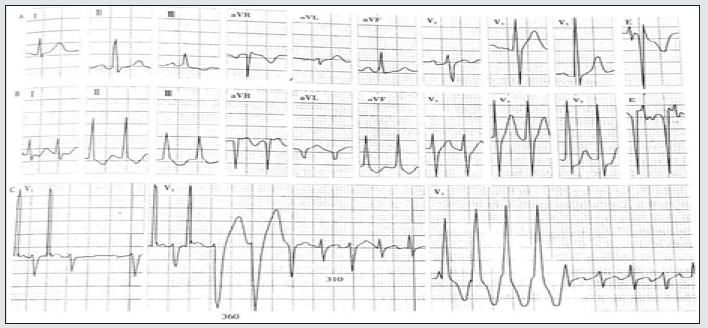

A 51-year-old male was presented with a history of Inferior Myocardial Infarction prior-8years documented with arrhythmia. He reports unbearable chest tightness several times a day, with night sweats disturbing his sleep. He presented hemodynamically stable at the outpatient clinic but was complaining of mild dizziness and palpitation. He uses beta-blockers for several years based on the doctor’s prescription but refused any syncopal history. The 12-lead ECG showed episodes of tachycardia deliberately with a reduced pulse rate. He was diagnosed with the ventricular preexcitation syndrome in the absence of SVT. To study the rhythm disorder in multiple blocked branches, an electrophysiology study was conducted to understand the morphological changes between the initial and terminal vector before and after ablation at the heart rate of 130 times/min. Before ablation, it shows PJ interval 0.24s and QRS 0.12 accompanied by ST-T changes showing no visibility of delta waves as shown in Figure 1. The QRS terminal vector relation is affected in the lead II, III, AVF, and V1+V2 lead.

A. Sinus rhythm, PR interval, and QRS cluster were normal

B. Directional atrioventricular re-entrant tachycardia

C. Esophageal atrial pacing fails to show bypass conduction. It induces atrioventricular reentricular tachycardia (Middle figure): the first two QRS of tachycardia presented left bundle branch block type, with RR period of 360ms, followed by QRS narrowing and R interphase 310ms indicating left latent bypass. Diagram of the mechanism of tachycardia in the center of the figure.

D. Atrial ventricular tachycardia presents wide and narrow QRS; if the time limit of wide QRS is longer, narrow QRS >35ms will be extended, indicating bypass and bundle branch bypass located on the same side, it is identified by the hidden left bypass. ECG- Sinus rhythm, atrioventricular re-entrant tachycardia with ipsilateral bundle branch block.